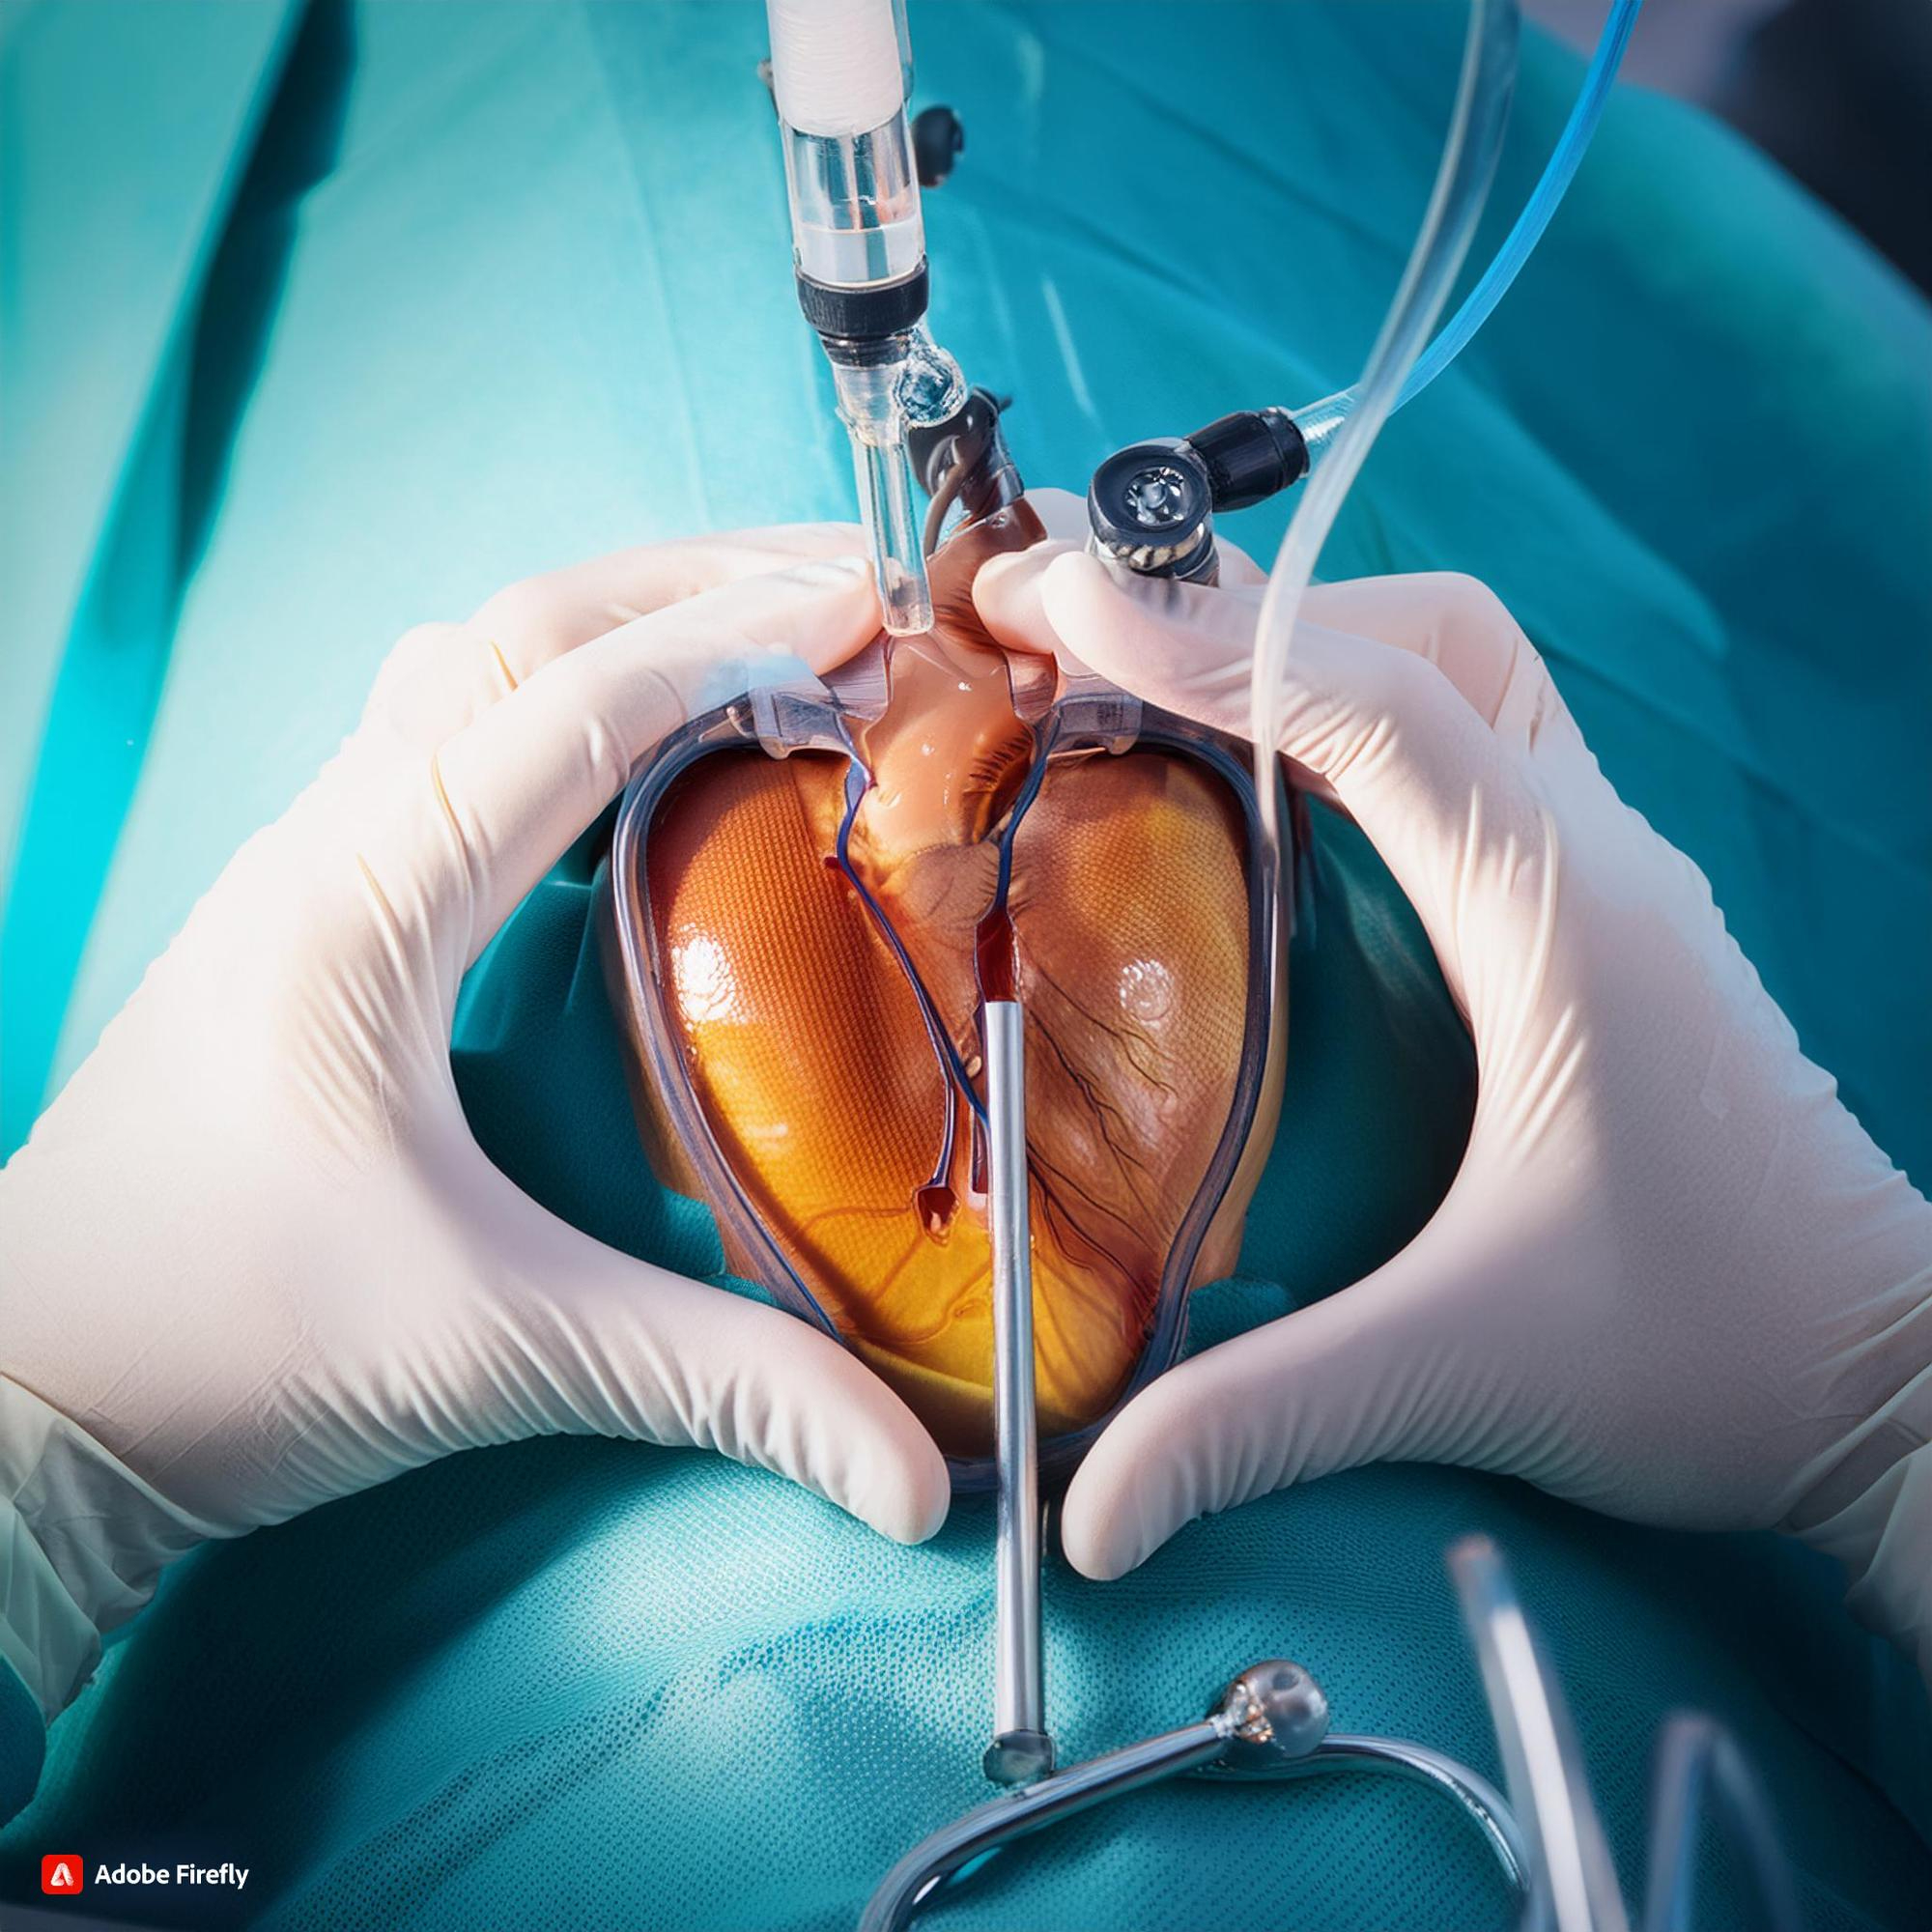

Multiple Modular OTs

Fully equipped operation theatres ensuring safe and infection-free surgeries.

Center of Excellence

From heart care to joint replacement, our super-specialities are led by expert teams and supported by the latest medical advancements.